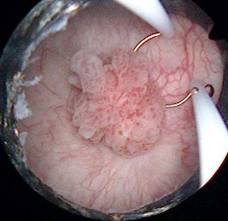

Екзофітний (пухлинний) тип-одиночний вузол, різний за величиною, блідо-сірого або коричневого кольору, поширюється до периферії. Має п’ять форм. - Крупноузелковая форма проявляється у вигляді щільних, які виступають над рівнем шкіри вузликів, полушаровидной форми. Процес поширюється до периферії, де місцями під шкірою промацуються щільні тяжі. Поверхня горбиста, на ній є телеангіектазії. Місцями з’являються депігментовані ділянки, що нагадують склеродерму.Конглобірованная форма- кілька щільних, які виступають над шкірою вузлів зливаються в одну групу. Окремі вузли мають вигляд напівкулі, поверхня горбиста. Під стоншеним покривним епітелієм розташовується мережу дрібних, розширених судин. У центрі вогнища є вдавлення, яке часто із’язвляется.

- Бородавчатая форма – щільний, виступаючий над шкірою напівкулястий вузол з папілломатознимі виростами на краях. У центрі вогнища бородавчаста, щільно прилипає рогова масса.

- Мелкоузелковая форма – група щільних вузликів, невеликих розмірів, що розташовується кільцеподібне. У центрі на вигляд здорової шкіри з’являються нові дрібні узелкі.

- Опухолево-виразкова форма представлена усіма вищезгаданими формами в більш пізніх стадіях, коли в центрі або по краях пухлини спостерігаються численні виразки, покриті корочками.

Виразковий тип базаліоми

- Роз’їдає виразка Джекоба (ulcusrоdеns) – поверхня виразки рівна, що не покрита нальотом, краї різко окреслені. Виразкові ураження може поширюватися на перехідні слизові (ніс, губа, повіку). Виразка покрита щільно прилягає коркової масою, без ознак запалення. Характеризується прогресуючим темпом зростання з деструкцією навколишніх тканин і органів (ніс, вуха, очі). Поверхня виразки глибоко западає, що говорить про поширення процесу в глубіну. Прободающая базаліома (Basaliomaterebrans) – рідкісний різновид, що характеризується різким западанием виразкової поверхні, покритої кіркою. Ознак запалення немає. Швидко деструірующім підлеглі тканини і завжди рецидивує після радикального лікування.